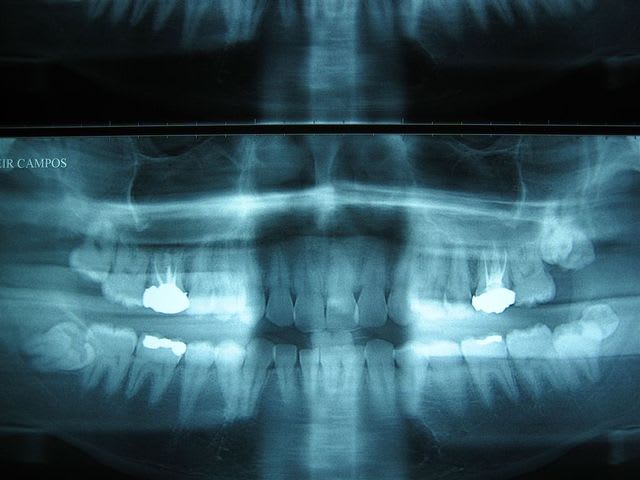

... j'ai profité de mes vacances _dernier jour aujourd'hui :((_ pour numériser ma collection d'OTP.

... premier cas: décharge de pistolet à grenaille dans le visage! (règlement de comptes entre toxicos)

Il faut dire qu'on soigne de drôles de pistolets chez nous!

... si vous aussi vous avez des OTP un peu particuliers ... postez!